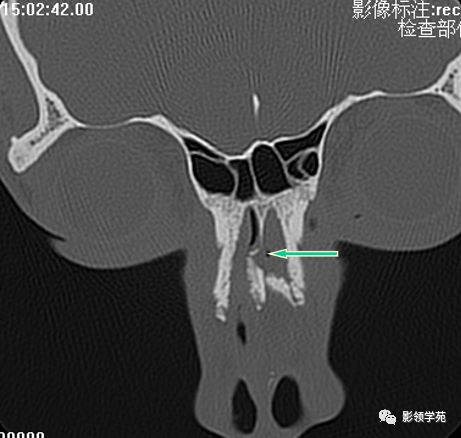

HRCT

- 冠状面:鼻骨长轴平行线

鼻骨冠状面HRCT

双侧鼻骨骨折

双侧上颌骨额突骨折

鼻中隔骨折